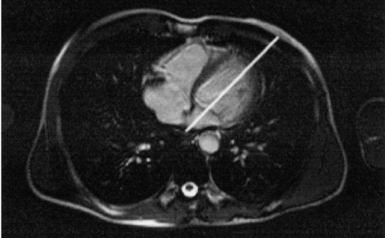

Figure 6.43 Axial, T1-weighted MR scan of left atrium.

Key: RV, Right ventricle; LV, left ventricle; LA, left atrium; RA, right atrium.